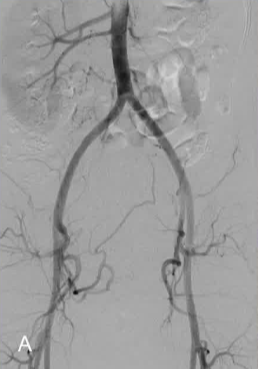

手术通过左侧桡动脉路径进行。 动脉造影显示右侧肾脏为单侧,右侧子宫动脉为单支,且左侧未发育的子宫角未获得明显的动脉供血。 通过一根微导管,使用直径为 500 - 700 微米的标定微球对右侧子宫动脉进行了栓塞,直至达到“修剪后的树状”终点位置。患者当天就出院了。 在三个月的随访中,患者表示所有症状都有所改善。

一例罕见的单角子宫伴症状性肌瘤病例,该病例通过子宫动脉栓塞术(UFE)得到了成功治疗。 在这种情况下,单独的一侧子宫动脉被进行了栓塞处理,取得了良好的临床效果,并没有发生不完全坏死。 虽然有关单侧子宫动脉栓塞术的疗效和效果的研究已有相关报道,但目前尚未有关于单动脉供血子宫肌瘤患者接受 UFE 手术的任何研究报道,此病例证实在左侧子宫动脉缺如的情况下,单纯栓塞右侧子宫动脉也可以达到完全坏死的情况。 1.Walker WJ, McDowell SJ. Pregnancy after uterine artery embolization for leiomyomata: a series of 56 completed pregnancies. Am J Obstet Gynecol. 2006 Nov;195(5):1266-71 | ||||||||||||||||||||||||